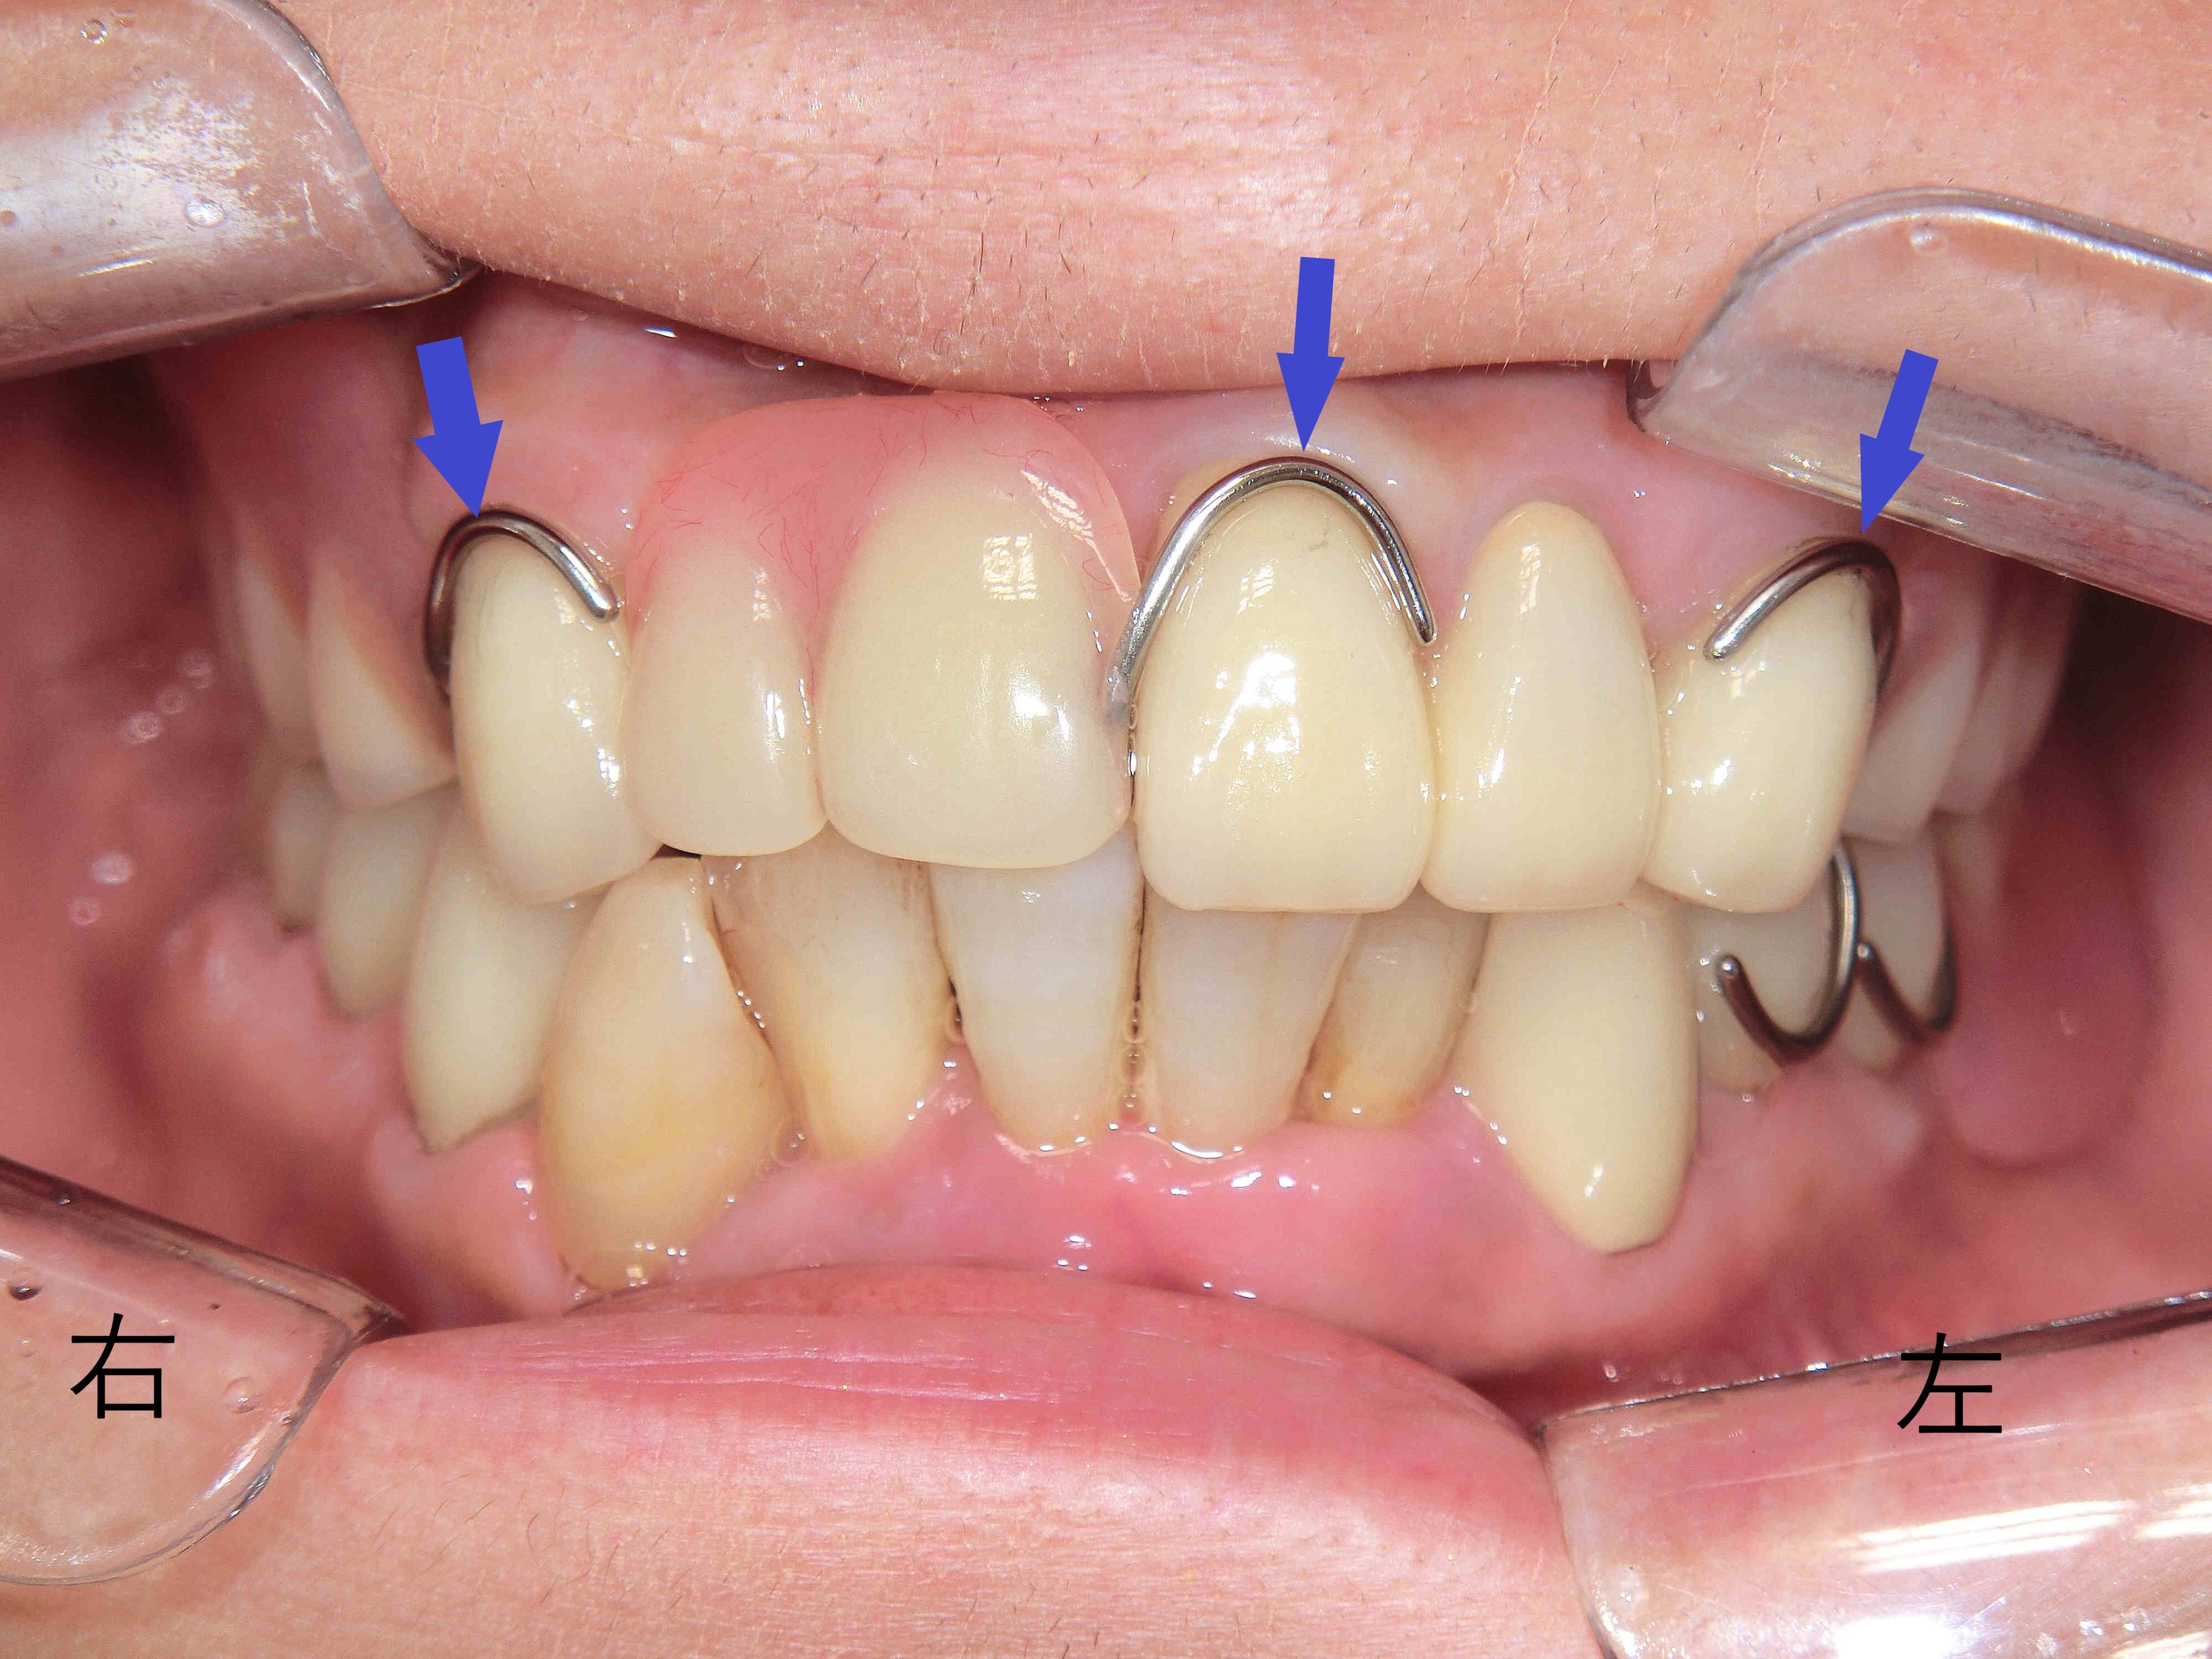

上下顎に保険適用の義歯を装着した状態を正面から撮影したもので、上顎には前歯しか残存歯がなく、その前歯に義歯を固定するため、金属製のバネ(クラスプ)を装着する必要がありました(青色矢印)。

前歯部に金属のバネがかかっているため、審美性が損なわれているのがわかります。